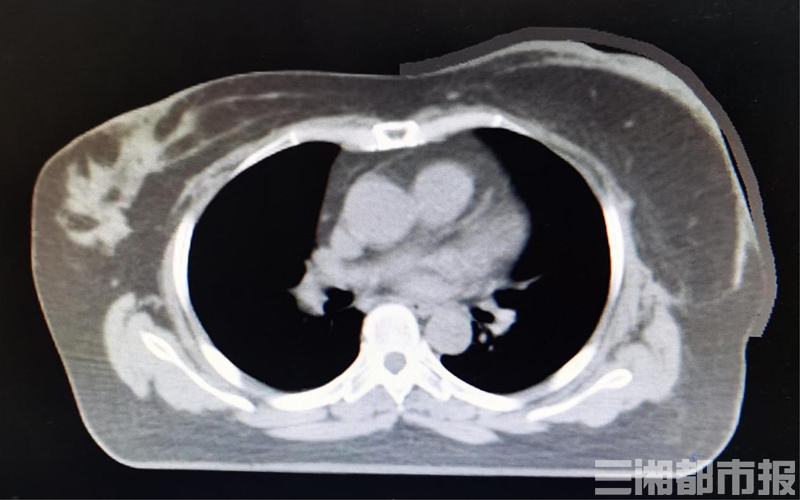

(上/常规组织补偿物与体表的空气间隙;下/3D打印组织补偿物与体表的控件间隙明显缩小)